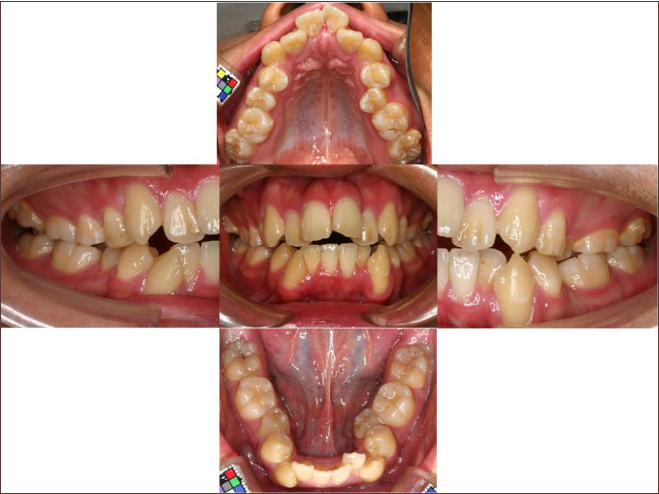

狭い歯列(狭窄歯列)によって、舌が歯列の中に収まらない状態です。

●高口蓋 ●低位舌 ●口呼吸

狭窄歯列(高口蓋)

狭窄歯列(低口蓋)

狭窄歯列(低位舌)

右のように、狭窄歯列だと舌は、狭い歯列に阻まれて、前方や上方の口蓋に自由に動くことができません。その結果、舌は低い位置(低位舌)にあり、前方に出ず後方に位置するので、気道が狭くなってしまっています。

一方、左のように、広い歯列だと舌は、前方にも上方にも自由に動けるので、舌は普段は口蓋についていて鼻呼吸が無理なくできているのです。

狭い歯列(狭窄歯列(きょうさくしれつ))

高口蓋(上顎が深い→鼻腔が狭い)

舌が歯列に納まらない→低位舌

歯並びが悪い

かみ合わせが悪い